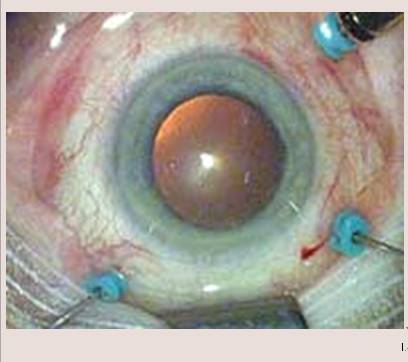

利器一:微创玻璃体手术

传统的玻璃体手术已有40多年的历史,操作复杂、手术创伤大、手术效果不确定。就像白内障手术的发展一样,眼科医生们不断改进手术方法,追求更安全有效、更微创的样式。现代玻璃体手术多采用25G或27G微创切口(见图6和图7),通过三个直径0.5mm-0.72mm的小针孔,技术精湛的医生在30分钟左右即可完成黄斑手术。术后三个小切口无需缝合,术眼舒适度高,几乎看不出手术遗留的疤痕。

图7. 25G玻璃体手术术中